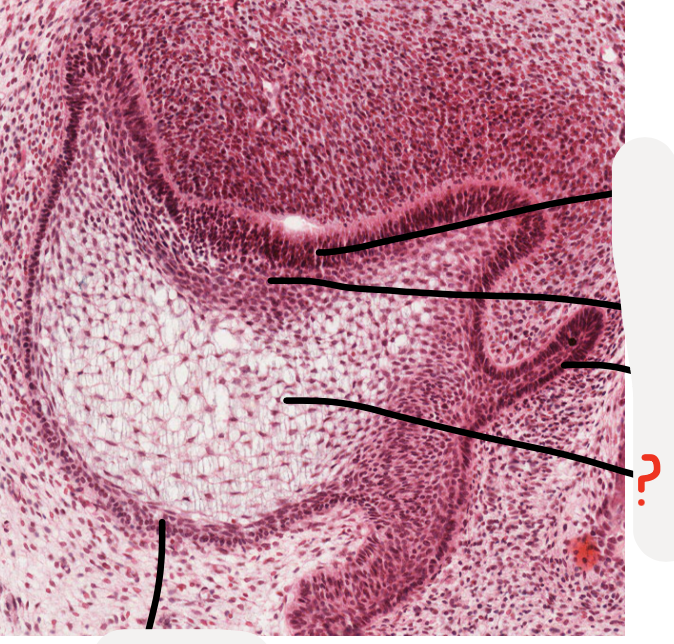

18

Q

A

vestibular lamina

19

inner enamel epithelium

20

stratum intermedium

21

successional lamina

22

stellate reticulum

23

outer enamel epithelium